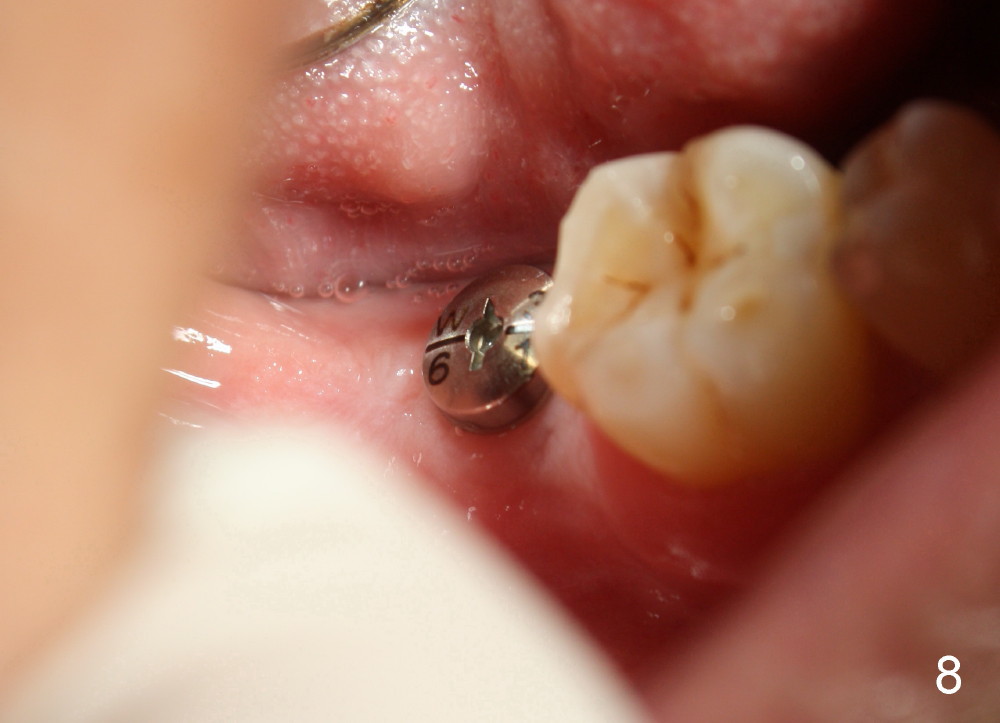

The implant is placed in the middle of the ridge buccolingually (Fig.6). A 6.2 x 3 (1) mm healing abutment is placed; the flaps tightly adapt to the abutment following suturing (Fig.7). The wound is then covered by perio dressing.

The wound heals uneventfully (Fig.8,9: taken 3 months postop). When an abutment is placed, there is no clearance for a crown. Two mini-implants are placed for the tooth #2 intrusion (Fig.10,11). Four months later, segmental orthodontic appliance is added because of lack of result of intrusion and buccoversion of the tooth #2 (Fig.12). Two months later, all of orthodontic treatment is terminated at the request of the patient. After heavy reduction of the tooth #2, a crown is cemented. Fig.13 (panoramic X-ray) is taken 11 months post cementation. There is no bone loss nearly 3 years post cementation (Fig.14).